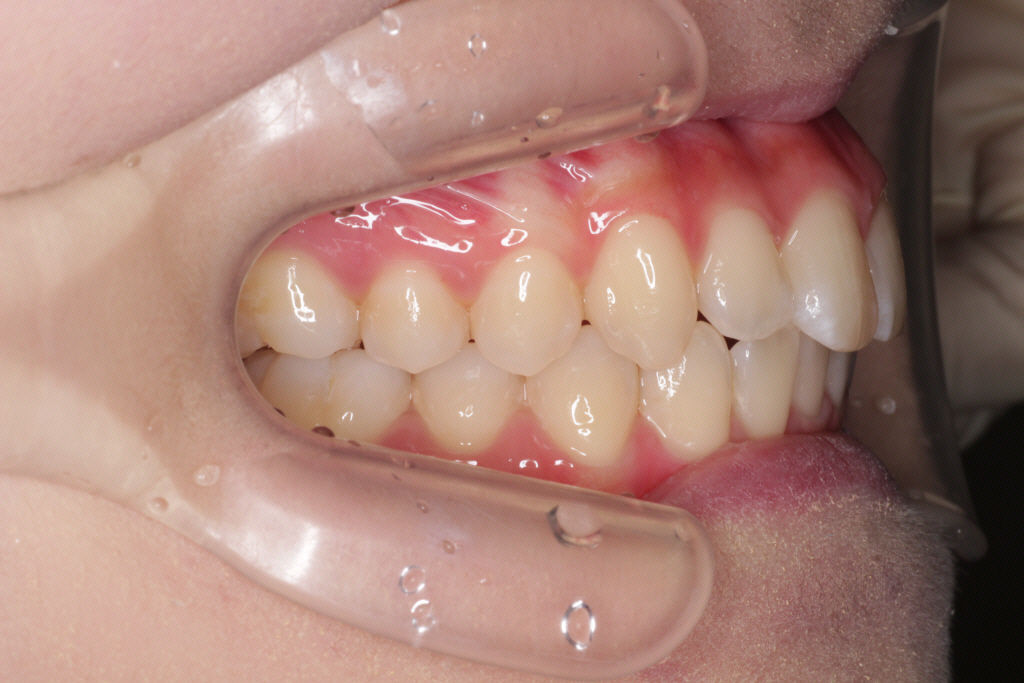

初診時のお口の中の状態です。↓

お口の中の状態としては

⑴咬み合わせが深い。(上の歯がかぶさっていて、下の歯が見えません。)

⑵右下の前から2番目の歯が叢生で歯列に入っていません。

⑶右上の前から2番目の歯が下の歯より前にありません。

診断:上顎前突・前歯部叢生